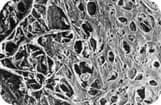

ALT spot size (left arrow) vs. SLT spot size (right arrow) on TM

Since Selective Laser Trabeculoplasty depends on the laser parameters for targeting the pigmented cells, it is not necessary to have a small spot size or to precisely target a site in the trabecular meshwork as compared to traditional Argon Laser Trabeculoplasty.

For SLT a large 400 micron spot is directed into the angle using a specially developed gonio lens to minimize beam distortion and provide good visualization of the angle. Unlike ALT, focus is not critical since the large spot has a greater depth of focus than the 50 micron ALT spot. A red aiming beam the same size as the treatment beam shows the area to be treated. Selective Photothermalysis determines which cells are targeted and activated.